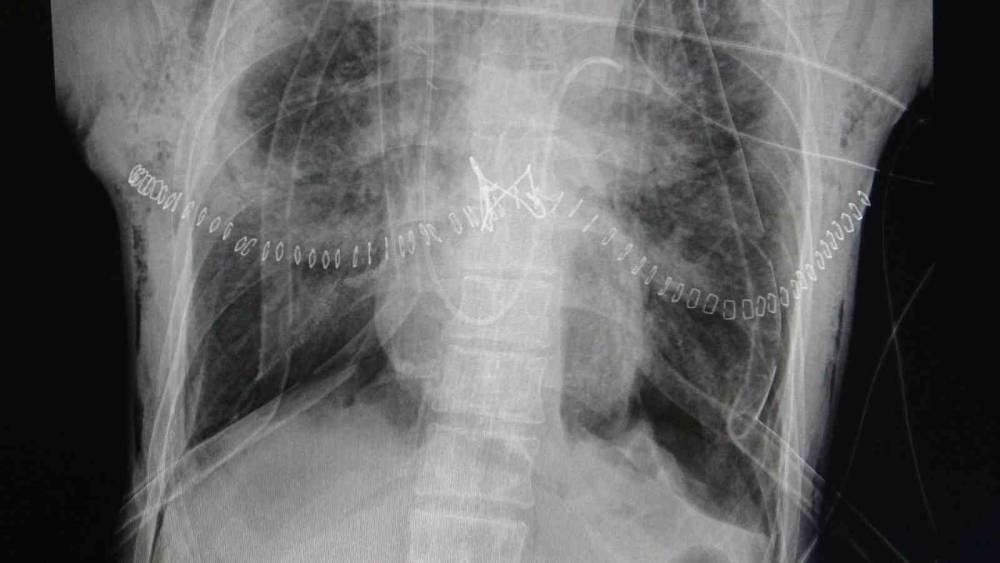

"Hastamızın yaşaması için tek çare nakildi"

Göğüs Cerrahisi Uzmanı Prof. Dr. Ahmet Erdal Taşçı, akciğer nakli bekleyen hastanın yıllardır bronşektazi hastalığıyla mücadele ettiğini belirterek, "Hastamızın yaşaması için tek çare nakildi. Nakil başarılı geçti. Bu operasyon, bizim ekibimiz için teknik anlamda standart bir akciğer nakliydi. Ancak dikkat çeken nokta, aynı anda hastanemizde bir karaciğer nakli operasyonunun da gerçekleştirilmiş olmasıydı. Aynı bağışçının organları, iki ayrı hastaya; biri akciğer, diğeri karaciğer olarak nakledildi. Bu vesileyle bağışçımıza Allah’tan rahmet, yakınlarına da sabır diliyoruz. Böylesine acılı bir anda başkasının hayatına dokunabilmek, örnek bir davranış" dedi.

"Yeni akciğerleriyle nefes alacak"

"Organ nakli, bir ülkenin sağlık sisteminin ne kadar gelişmiş olduğunu gösteren önemli bir göstergedir." diyen Taşçı, "Ameliyatı gerçekleştirilen hastamız, yoğun bakımda uyanık ve solunum desteğiyle izleniyor. Kısa sürede yeni akciğerleriyle nefes alması bekleniyor" diye konuştu. Taşçı, "Türkiye’de özellikle kadavra donör organ bağışlarının artması büyük önem taşıyor. Herkesin bir gün kendisinin veya sevdiklerinin de bu ihtiyaca düşebileceğini düşünerek, organ bağışı konusunda daha duyarlı ve bilinçli hareket etmesi gerekiyor. Ülkemizde Sağlık Bakanlığı’nın bu alandaki organizasyonu ve altyapısı gerçekten çok iyi seviyede. Bu anlamda emeği geçen herkese teşekkür ediyoruz" ifadelerini kullandı.